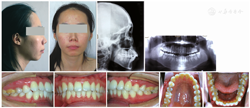

患者 女,27岁,主诉:"嘴突",要求矫正。患者全身健康状况良好。自述年幼时曾于外院有过非拔牙正畸治疗史,近年来发现嘴越来越突。

正面观:面部左右对称,面上、中、下部比例协调,鼻孔朝上,暴露过多,口唇前突,闭唇紧张;侧面观:呈凸面型,颏唇沟不明显,鼻唇角大。

恒牙列,18、38、48全部或部分萌出,28未见;双侧磨牙及左侧尖牙中性关系,右侧尖牙略偏远中;前牙覆

正常,覆盖约5 mm;上牙弓呈卵圆型,无明显拥挤,下牙弓呈方圆型,拥挤度约4 mm;上中线居中,下中线右偏约1.5 mm。

X线片未见28牙胚,左侧关节头形态欠佳,与右侧关节头不对称,牙周情况良好。

头影测量表明患者为骨性Ⅱ类,高角,上下前牙唇倾,唇部前突。